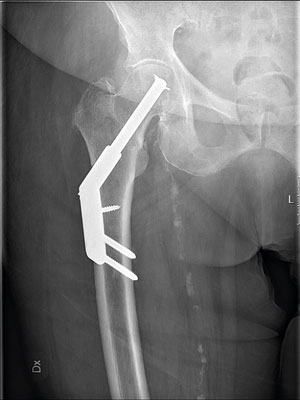

Pertrokantära frakturer opereras med kort märgspik eller glidskruv och platta. Trenden i Sverige de senaste åren är att fler opereras med märgspik. Vid stabila frakturer väljer de flesta att operera med glidskruv och platta. Vid instabila frakturer, bl a splittrade flerfragmentsfrakturer, föredrar många att operera med kort märgspik. Det finns ingen säker evidens för att den ena metoden är bättre än den andra [13-15].

Till vänster en icke-opererad pertrokantär fraktur och till höger en som är opererad med glidskruv och platta. God reposition är mycket viktig för frakturläkningen.